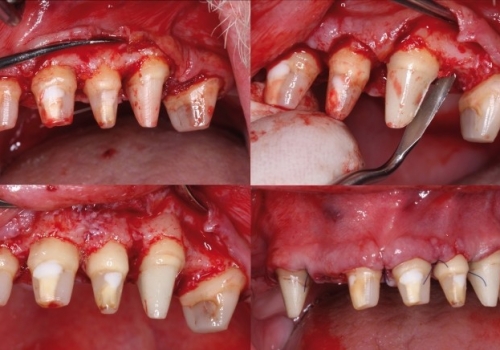

Bundan başqa, travma, ciddi karioz zədələnmə, normadan artıq preparasiya (diş yonulması) və s. nəticəsində diş tacının böyük ölçüdə dağılması zamanı bu dişlərin üzərinə qapaq, körpü konstruksiyalarının hazırlanması və ya bu dişlərin çıxan diş konstruksiyaları üçün (məsələn: teleskopprotezlər) fiksasiya elementi olaraq hazırlanması mümkün olmur. Buna səbəb diş toxumasının normadan artıq dağılmasıdır. Bu zaman tətbiq edilən metodlardan ən başlıcası diş tacının cərrahi uzadılmasıdır. Bu metodun tətbiqi ilə sümük müəyyən miqdarda uzaqlaşdırılaraq dişin tac hissesi uzadılmış olur. Nəticədə protetik olaraq yararsız diş yararlı duruma gətirilir.